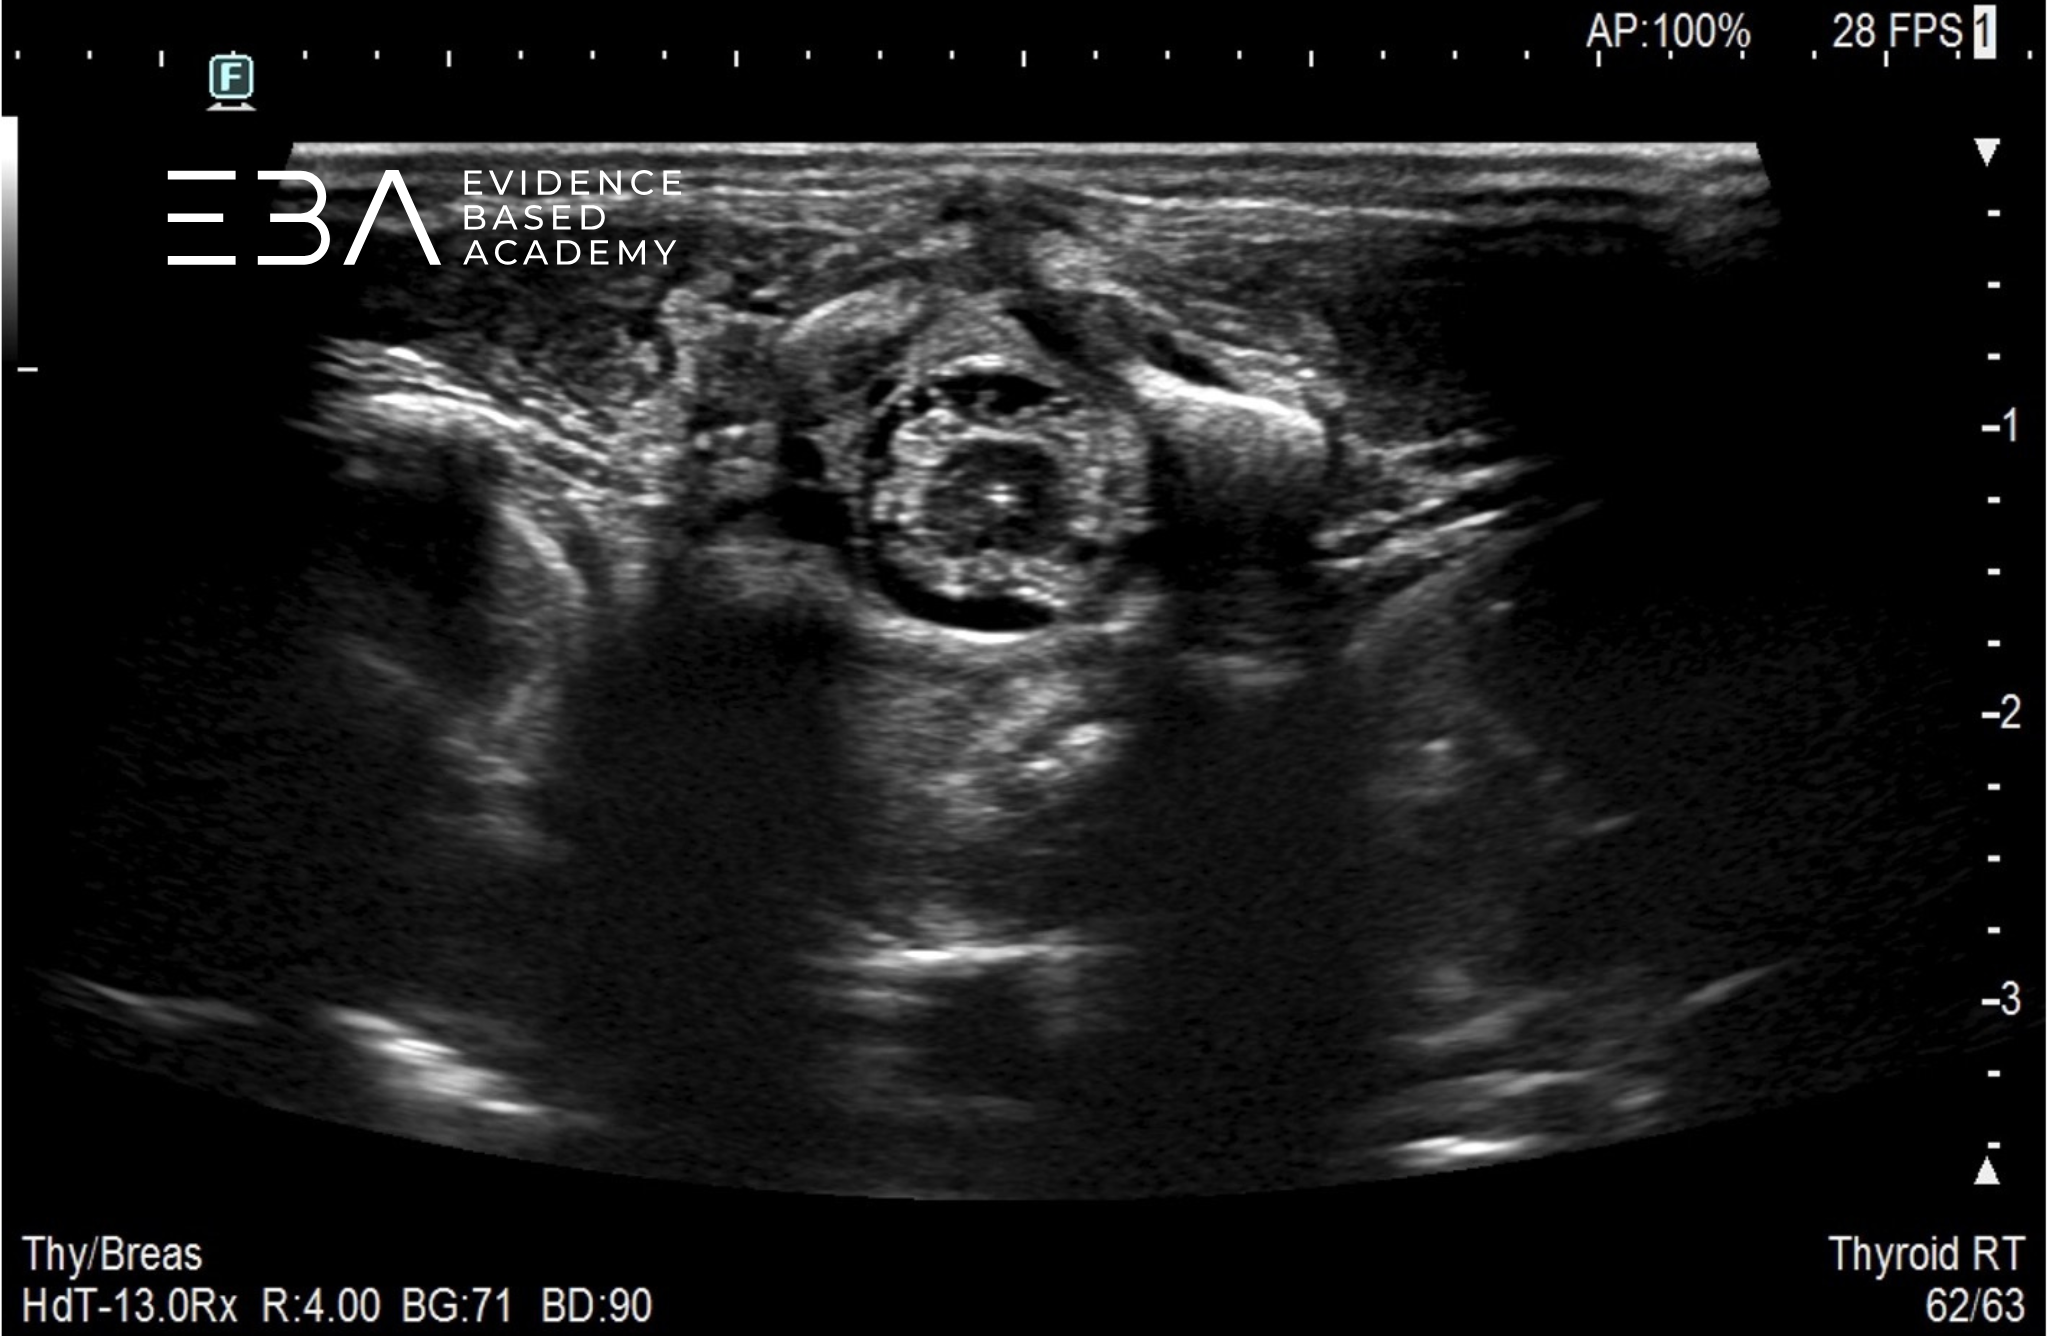

fot. 6

Przekrój poprzeczny kanału kręgowego na wysokości odcinka lędźwiowego.

fot. 7

Przekrój poprzeczny kanału kręgowego na wysokości drugiego kręgu lędźwiowego (L2) widoczny jest koniec stożka rdzenia kręgowego.